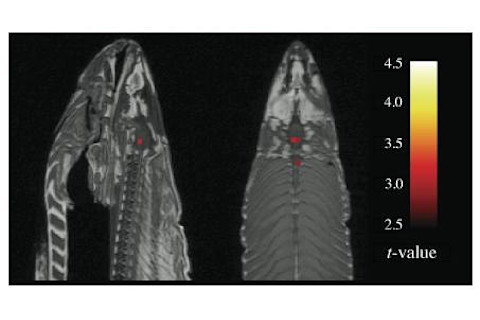

This is a poster presented by Bennett and colleagues at this year’s Human Brain Mapping conference. It’s about fMRI scanning on a dead fish, specifically a salmon. They put the salmon in an MRI scanner and “the salmon was shown a series of photographs depicting human individuals in social situations. The salmon was asked to determine what emotion the individual in the photo must have been experiencing.”

But not everyone uses multiple comparisons correction. This is where the fish comes in – Bennett et al show that if you don’t use it, you can find “neural activation” even in the tiny brain of dead fish. Of course, with the appropriate correction, you don’t. There’s nothing original about this, except the colourful nature of the example – but many fMRI publications still report “uncorrected” results (here’s just the last one I read).